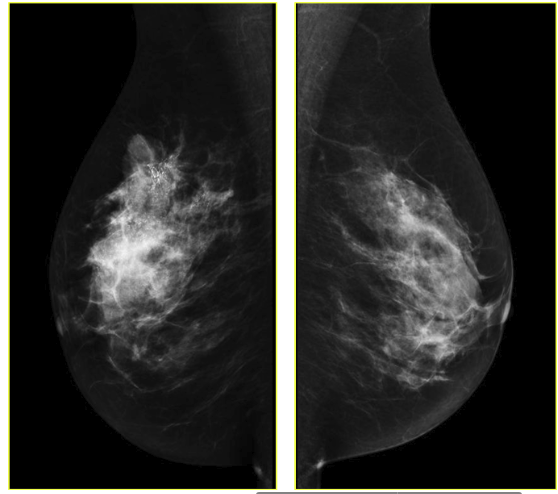

However there is also a novel technique developed in the last few years based on the mammography methodology: contrast-enhanced spectral mammography (CESM). This method, like MRI, is based on imaging of tumor neoangiogenesis by use of a contrast agent [1, 13]. CESM uses a chelated iodine-base x-ray contrast agent, while MRI uses a chelated gadolinium-based paramagnetic agent [14, 15]. Because of high sensitivity of CESM (similar to sensitivity of MRI) this technique maybe comparable with MRI in some cases. CESM, like other diagnostic methods, has some limitations. Benign lesions enhance on CESM, just as they do on MRI. That is, there is no possibility to generate a time-enhancement curve, comparable to that in breast MRI [11, 16]. Just as with mammography, CSEM sensitivity and specificity also varies depending on the age of the examined group and number. Sensitivity and specificity varies from 92.7% to 100% and 41% to 69.7%, respectively [11]. Exemplary CSEM images for CC and MLO views are shown in Fig. 2.